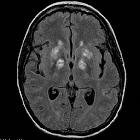

HIV/AIDS (CNS

manifestations) • Cerebral toxoplasmosis - Ganzer Fall bei Radiopaedia

The CNS manifestations of HIV/AIDS (neuroAIDS) occur secondary to a wide range of neurodegenerative, infectious, inflammatory, or neoplastic processes.

Opportunistic infections

- toxoplasmosis (most common)